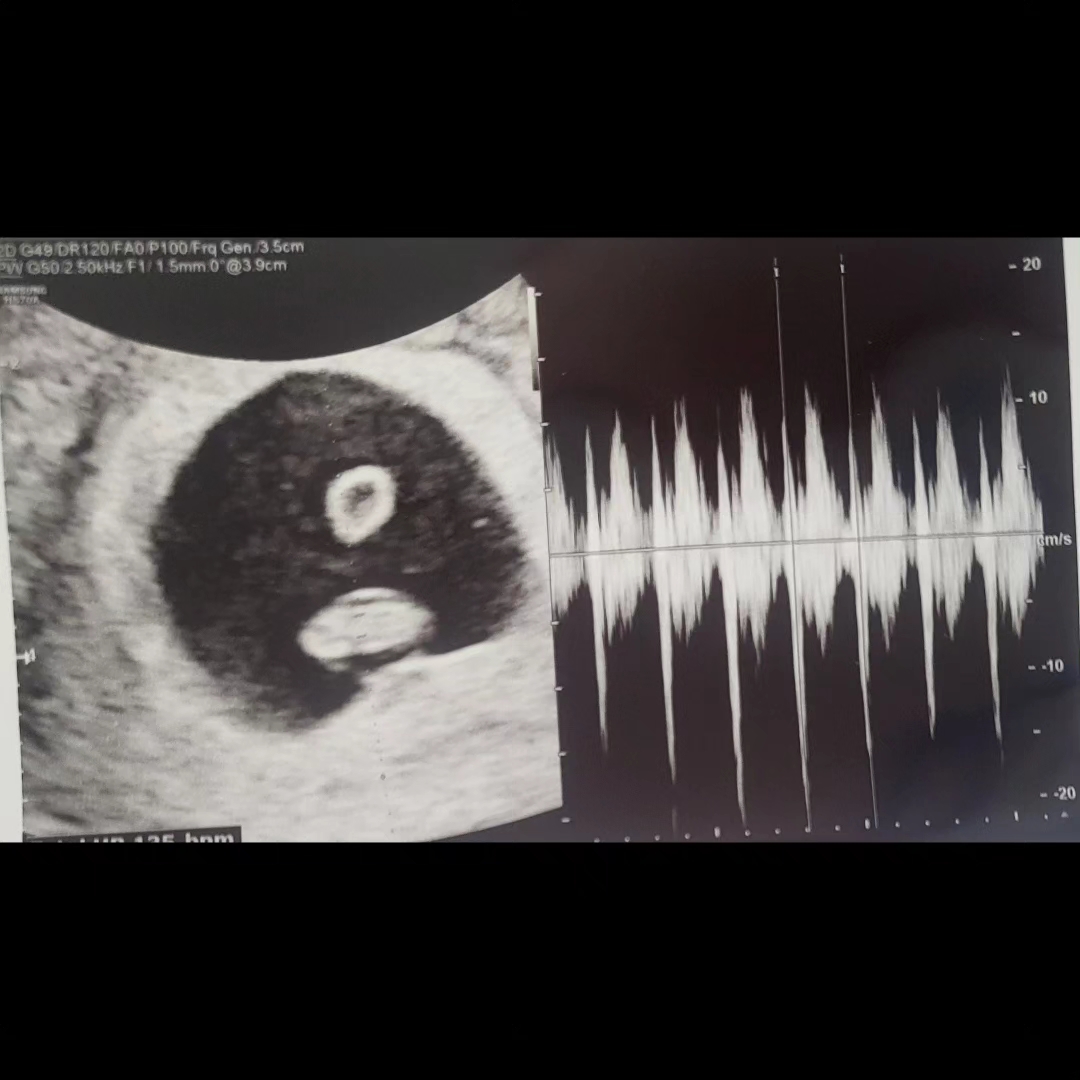

난황위치로 성별보시던데요!

전 아무리봐도 즁간같은데...

첫째는 딸인데 아들위치여서 ㅋㅋ 둘째는 확연히 또 반대편에 있는데 어떨지 모르겟어요ㅎㅎ 아들은 14주 촘파만 봐도 대부분 알더라구요😆 이제 얼마 안남앗자나요~~